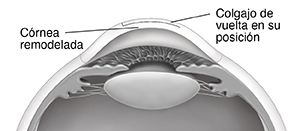

El cirujano usa un láser excimer guiado por computadora para remodelar la córnea. La parte del procedimiento que comprende el tratamiento con láser dura unos 10 a 90

segundos.

Se coloca el colgajo en su posición. El tejido corneal se adhiere a sí mismo mientras se cicatriza.